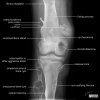

Bone Tumours

Very informative illustration pertaining to Bone Tumours by Matt Skalski @docskalski on twitter. Bone Tumours – Labelled